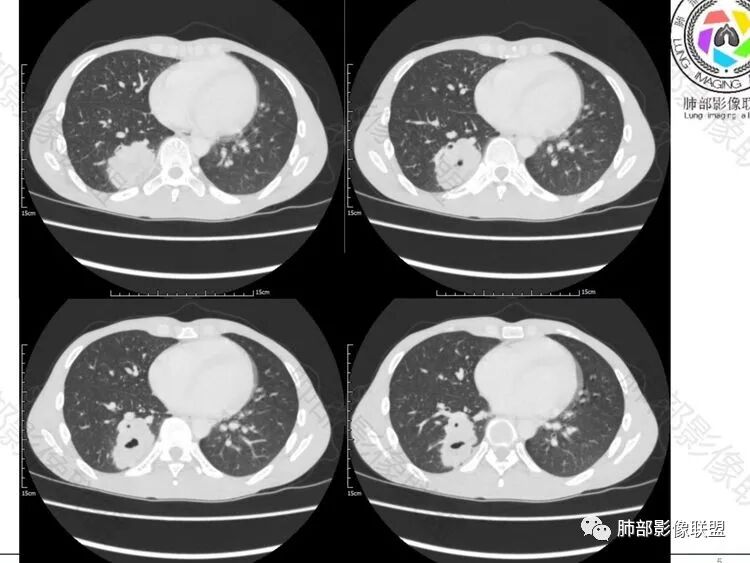

【每日晨读】中青年张牙舞爪的肺包块

右肺下叶背段实变影,宽基底与胸膜相连,边缘毛糙,内部可见空洞影,空洞壁光滑,内部可见坏死,近端支气管显示不清,远端胸膜下间隙可见,青年男性,考虑结核,鉴别NTM,鳞癌

青年男性,呼吸道症状起病,右肺下叶背段肉芽肿样变,边缘分叶,胸膜糊墙,略牵拉,内部密度不均,空洞无物,壁整,支气管通畅,卫星灶,玫瑰结状小叶中心性结节及少量树芽;中度强化,湖泊样坏死,内部无完整血管影:结核可能性、鉴别:坏死性支原体肺炎、鳞癌。

有晕征,第一感觉像是感染类病变,仔细看下叶支气管不通畅,感觉有阻塞,先考虑感染类病变,肺链?隐球?毛霉曲霉?TB?NTM?鉴别诊断肉瘤类,肉瘤样癌,类癌。

青年,咳嗦,指标基本正常,右肺下叶不规则软组织密度影,密度不均,有坏死,小空洞,宽基底与胸膜相连,支气管觉得通畅,考虑感染,鉴别结核

35岁男性患者,病史及实验室检查无免疫受损相关依据,无感染毒血症状,炎症指标CRP、降钙素原、血沉均正常,曲霉抗原阴性;CT提示右下背段肿块影,边缘膨隆,有分叶及短毛刺,偏心空洞,增强扫描提示不均匀强化,有坏死,考虑:1.腺癌 2.隐球

中年男性,咳嗽2月余,pct正常,首先排除普通肺炎。右下背段肿块,边缘毛糙,浅分叶,与胸膜宽基底相连,有坏死(无液平,为凝固性坏死,不考虑脓肿),常规考虑结核隐球菌,鉴别恶性肿瘤

青年男性患者,间断咳嗽、少量黄白痰2月,胸部CT:右肺下叶后基底段类圆形病灶,边界清楚,周围磨玻璃,内部有空洞形成,空洞干净,考虑炎性病变,脓肿,隐球,结核,鉴别鳞癌

右肺下叶肿块,分叶,近端支气管部分堵塞,部分沿壁厚,沼泽样强化,可见空洞,邻近胸膜少量积液,膈肌牵拉,考虑肿瘤,鳞癌?鉴别NTM

青年男性,慢性病程,右肺下叶团块影,形态不规则,内见空洞,壁厚薄不均,不均匀轻度强化。考虑恶性,肺癌,肿标中角蛋白19增高,倾向于鳞癌,鉴别结核。

中年男性,有咳嗽咳痰病史俩月,亚急性病程,炎性指标不高,右肺下叶后基底段近胸膜下不规则肿块,边缘膨隆毛糙,支气管近端阻塞,内有厚壁空洞,无液平,洞壁不均匀强化,周围支气管壁厚,远端有点片影,考虑鳞癌可能性大,鉴别肺脓肿和肺结核。但是血沉不快,crp不高,有点不大符合炎性。

看一下病灶主体,支气管堵塞

1.支气管截断

2.边缘模糊磨玻璃。

3.形态主体有明显膨隆,边缘有很多散发的病变边缘平直

4.远端有树丫,提示炎症一定存在的

5.淋巴结稍大

6增强后有很多坏死,与实性成分分界不清

7.脐凹?

结合年龄主要考虑的有:肺癌,与之非常相似的结核和隐球菌。。。隐球菌应该强化比较均匀不符合。主要是肺癌和结核鉴别,年轻,空洞,树丫,结核是需要考虑。但是边缘膨隆,强化不均匀,支气管堵塞,可疑脐凹,这些都比较支持恶性,建议支气管镜吧,比较少见的坏死性肉芽肿还有放线菌这种慢性炎症。

11-20晨读病例结果:穿刺病理回报鳞癌(未拿到免疫组化结果)(张硕老师提供)